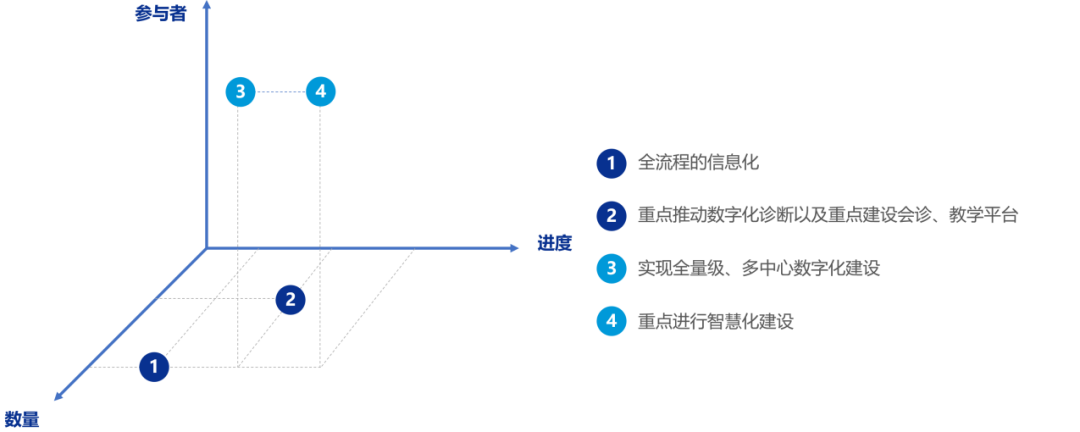

数字化智慧病理科建设指南:分级建设是核心主旨

分级建设方案